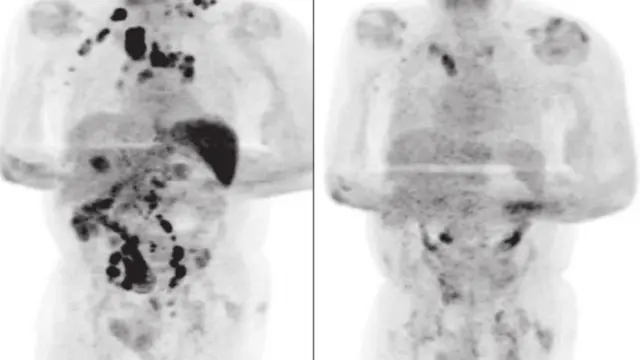

Lo que ha sorprendido a la comunidad científica es que tras recuperarse del virus, a los cuatro meses el hombre acudió al médico para una revisión del linfoma que padecía y las pruebas evidenciaron una disminución radical del tamaño de los ganglios afectados y una notable mejoría.

La principal hipótesis de los investigadores apunta a que la infección por SARS-CoV-2 desencadenó una respuesta inmunitaria antitumoral: las citocinas inflamatorias producidas en respuesta al virus podrían haber activando células que actuaron contra el tumor.